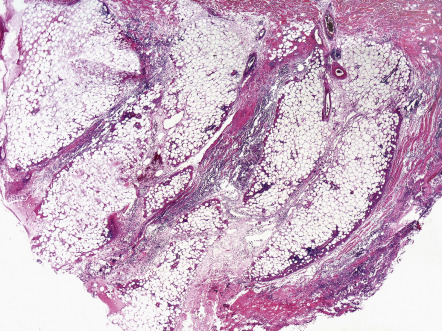

Table 100.7 outlines the microscopic changes in morphea- and scleroderma-associated septal panniculitis ( Fig. 100.4 ). Lymphocytes and plasma cells predominate , although macrophages and eosinophils may be present. In some cases, the number of plasma cells is striking . In late stages of morphea, the subcutis is largely replaced by hyalinized connective tissue, very often accompanied by changes of lipoatrophy.